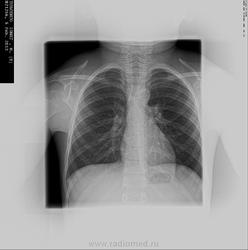

Добрый день.Помогите разобраться в снимке ребёнка (7,5 лет).Рентгенолог поставил диагноз:много мелких кальцинатов.

И где же он нашел много кальцинатов?В корнях?

да ,в корнях дёгких,а что бы вы сказали по поводу снимка?

Если у ребенка находят кальцинаты в корнях,то,как правило одним обзорным снимком дело не заканчивается.Ставится диаскин-тест и выполняются тмг ч/корни или КТ гр.кл.Дело идет в выявлении активности туберкулеза ВГЛУ.Что-то еще помимо R-граммы гр.кл.вам сделали?

Да,вчера сделали томограмму и оказывается никаких патологий не обнаруженно,кровеносные сосуды доктор принял за кальцинаты.Вот так иногда у нас ошибаются врачи?